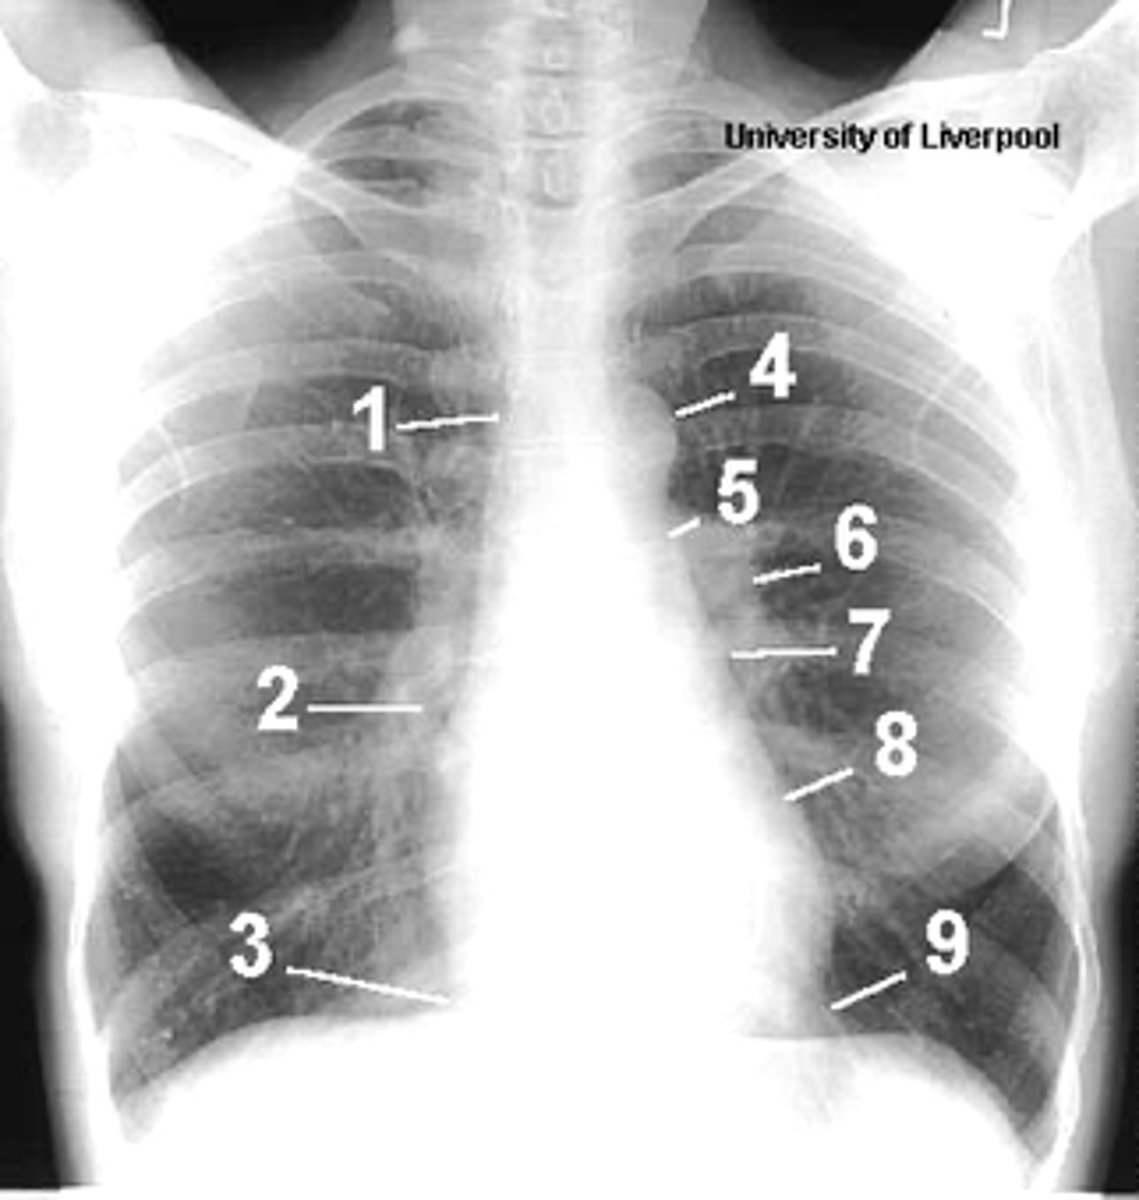

1

superior vena cava

2

right atrium

3

inferior vena cava

4

aortic arch or knob

5

left pulmonary trunk

6

left pulmonary artery

7

left atrium

8

left ventricle

9

left cardiophrenic angle